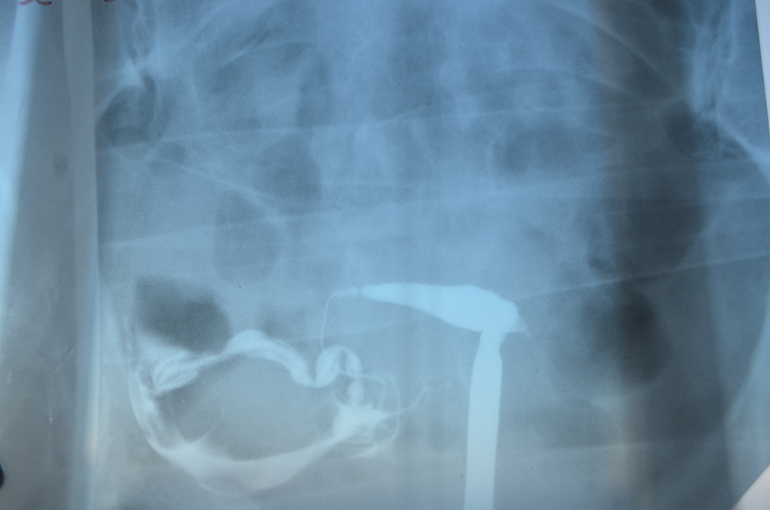

Результаты МСГ

ГСГ, ЭХО, МСГ, ФертилоскопияДевочки, как по Вашему мнению, у меня трубы проходимы? Какая вероятность забеременеть с такими трубами?

Врач ответила что трубы проходимы, но очень длинные и со спайками, настрого запретила планировать и назначила массаж(